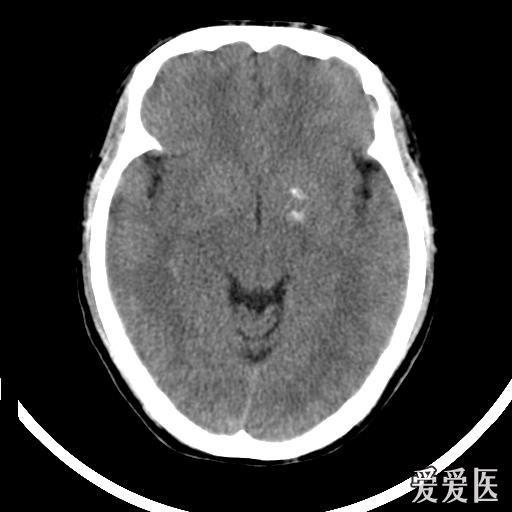

正常脑ct {b}. 苍白球钙化 {c}. 腔隙性脑梗死 {d}. 脑出血 {e}.

11. 可见双侧尾状核,苍白球及皮层下白质对称性高密度影

钙化,转移性钙化病理性钙化右侧尾状核头钙化,呈结节状双侧苍白球钙化

双侧基底节钙化,如何诊断?